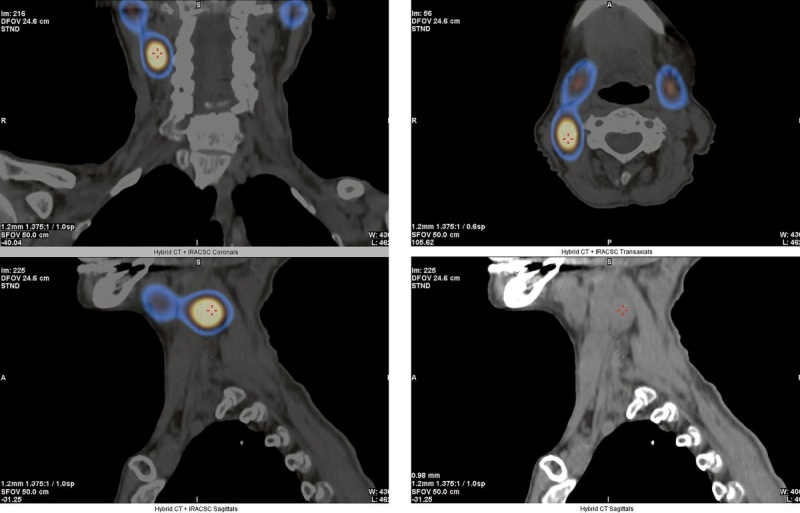

Topical diagnosis can be severely complicated in patients with primary hyperparathyroidism (PHPT) due to the ectopic placement of parathyroid gland (PTG) formations. We report a clinical case of PHPT in an 84-year-old patient caused by ectopic PTG adenoma located behind the right internal jugular vein at the level of the right submandibular gland. The impossibility of surgery for a long time due to the absence of a topical diagnosis has necessitated conservative treatment was required to get the hypercalcemia under control. In view of the concomitant deficiency of vitamin D, an attempt was made to use therapy with saturating doses of cholecalciferol under dynamic monitoring of the indicators of phosphorus-calcium metabolism, which allowed to achieve a significant decrease in PTH levels while maintaining normocalcemia.